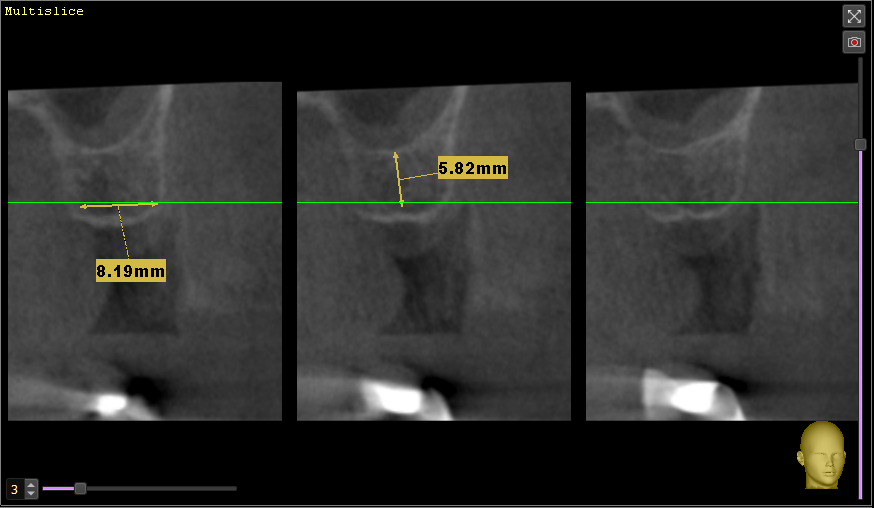

ЕвгенийПет Опубликовано 30 ноября, 2023 Поделиться Опубликовано 30 ноября, 2023 (изменено) Доброго дня! Уважаемые врачи, проблема и вопросы у меня в следующем: Примерно в 2010 году пришлось удалить 26 и 27 зубы (сначала свищ на одном, а со временем (около года) уже не помню почему и второй. С тех пор жую только на правую сторону, а сейчас под удаление 15 (снимок №1 во вложении), весной отекло лицо, обнаружили гранулему и вскрывали абсцесс. Тоже вопрос, хотя даже я по снимку вижу, что его не спасти, но а вдруг? Так вот, с жеванием теперь возникнут явные проблемы (отсутствует 46 зуб), и нужно срочно что-то решить со вторым рядом. Сразу скажу, что импланты сейчас не могу себе позволить, так как в прошлом году делал КТ, показывал хирургу, он сказал, что там перфорация и обязательно нужен синус-лифтинг (снимок №2 во вложении). Посмотрите, пожалуйста, это реально так? Без синус-лифтинга точно никак? Основной вопрос (снимок №3 вчера сделал) - врач предлагает сделать консольный мост с тремя коронками - с вкладкой на 24, закрыть 25 и созданный 26. Сразу скажу, что прошлым летом перелечивал канал в 24 и ставил на него металлокерамику на двух штифтах (один уже был ранее, второй добавили), но она сломалась месяц назад, чуть более года (из-за этого у меня вообще недоверие к коронкам, у меня 35 зуб только корень, на нем сделана пломба, и он стоит уже 7 лет без проблем). Первый основной вопрос - хорошо ли пролечены каналы в 24 и 25 зубах под мост? И второй основной вопрос - насколько будет прочна конструкция консольного моста, с учетом отсутствия 27? какие риски продолжения разъезжания ряда (за эти 14 лет эта сторона и так уже прилично разъехалась)? Момент еще в том, что сильно выросли за это время 36 и 37 зубы, там буквально милиметр остается для новых 26 и 27 зубов. Ранее другой врач мне советовал сделать мост с опорами на 28 и 24+25, но текущий врач такое даже не рассматривает, говорит, что 28 кривой уже (не депульпирован) и такая конструкция сломается быстро, а консольный 24+25+26 будет надежнее. Прошу помощи и консультации, что можно сделать в данной ситуации кроме имплантов. Заранее благодарю! И менее важный вопрос - позавчера депульпировал 36 зуб, посмотрите, пожалуйста (снимок №4), хорошо ли пролечены каналы? Спасибо! Изменено 30 ноября, 2023 пользователем ЕвгенийПет Ссылка на комментарий

wladdX Опубликовано 6 декабря, 2023 Поделиться Опубликовано 6 декабря, 2023 Измерения в зоне 26 и 27 2 Ссылка на комментарий